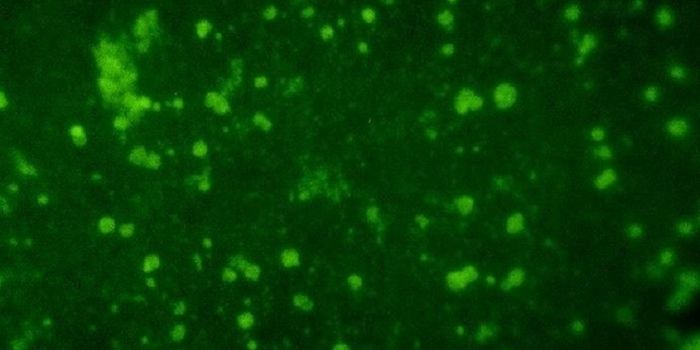

FEB 21, 2023Cell & Molecular BiologyThe Griffith Lab at UNC discovered telomeric protein & potential biomarker VR (green), shown in the nuclei (blue) of hum ...